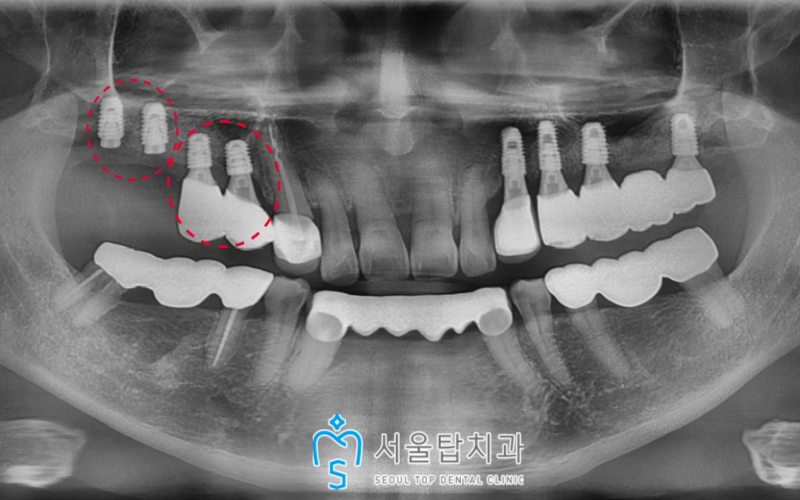

오른쪽 어금니 자리도 인공치근이

뼈에 잘 유착된 것을 확인한 후

보철 과정까지 마무리 해드렸습니다.

양측 모두 임플란트 치료를

성공적으로 마무리 해드린 모습입니다!

🦷 치료전 🦷

🦷 치료후 🦷